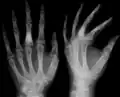

Corticoplasty has been shown to have success in treating hand lesions and deformities while retaining normal function.[23][24] The surgery utilizes the removal of tissue (curettage) and bone reconstruction in order to remove enchondromas and improve cosmetic appearance. Many cases of corticoplasty have been shown improvement in appearances while maintaining function. Recurrence of enchondromas was observed in some cases. In cases of Ollier disease, early surgical treatment of enchondromas in the hand is recommended.

X-ray showing calcified enchondromas localized in finger a 37-year-old patient affected with Ollier disease -